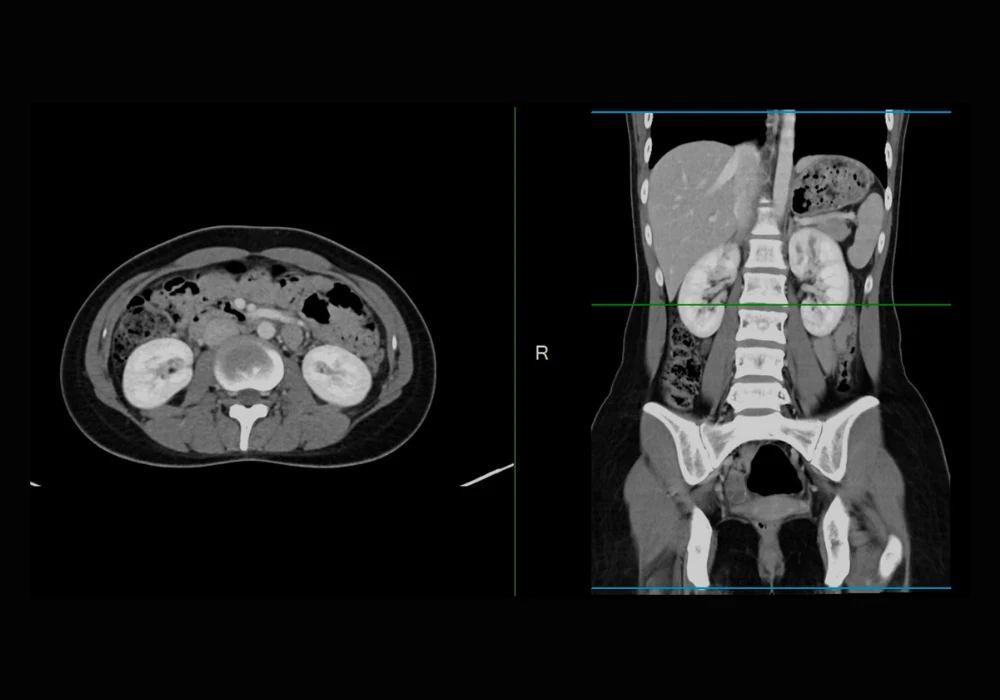

Accurate protocol selection for abdominal CT examinations is a critical component of radiology practice. Appropriate configuration of acquisition parameters and effective use of contrast media depend on choosing the correct protocol, which directly influences diagnostic precision and clinical outcomes. Despite its importance, the task of protocolling remains highly resource-intensive. Radiologists, trainees and technologists are routinely responsible for assigning hundreds of CT protocols each week, which contributes significantly to noninterpretive workload. These frequent interruptions not only consume valuable time but also divert attention from image interpretation, creating operational challenges for efficiency and focus.

To assess the viability of LLMs in this context, 300 consecutive abdominal CT requisitions for adult patients were analysed. These cases, submitted in April 2024, included a balanced representation of emergency, inpatient and outpatient settings. De-identified requisition data, including free-text clinical indications, were processed using three distinct LLMs: GPT-4o, o1-mini and o3-mini. The models operated through a vendor-provided application programming interface (API), using a shared system prompt embedded with few-shot examples and institution-specific guidelines. Each model produced a protocol assignment, a triage priority and recommendations regarding the use of intravenous and enteric contrast media.

Two experienced abdominal radiologists established consensus reference standards for each case. These standards encompassed 20 unique protocol types, with routine abdomen-pelvis, chest-abdomen-pelvis and renal colic protocols being most frequently assigned. Performance was evaluated based on exact match accuracy with the reference standards. The top-performing model, o1-mini, achieved an accuracy of 87.7 percent for protocol selection, 83.0 percent for priority assignment, 92.3 percent for intravenous contrast recommendations and 91.7 percent for enteric contrast media suggestions. The remaining two models performed comparably, with no more than 1.5 percentage points difference across any task.